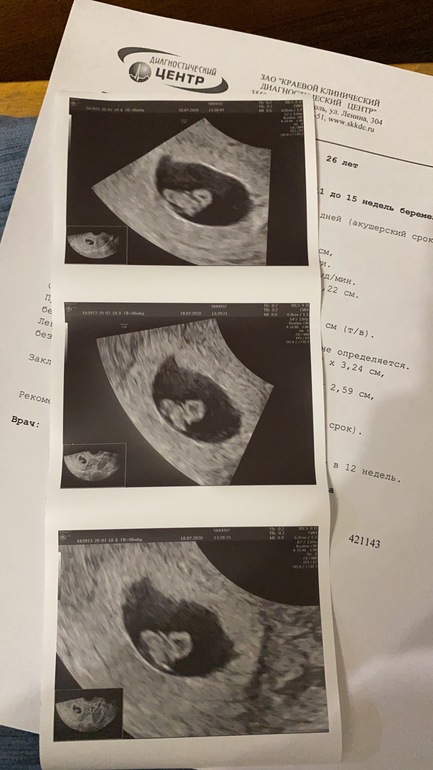

Я БЕРЕМЕННА !Всем привет🌹😚сегодня ходила на повторное узи , я увидела своего малышончика такого шладкого 😊😍моя крошечка 🙏🙏🙏😭Уже не крошечка😅!! 5 дней тянет живот , тонуса нет , папаверин не помогает, видемо малыш растёт и поэтому тянет (мои предположения) по Узи 🙂пу пу всё хорошо ☘️👼🏻🤰24.07 иду вставать на учёт